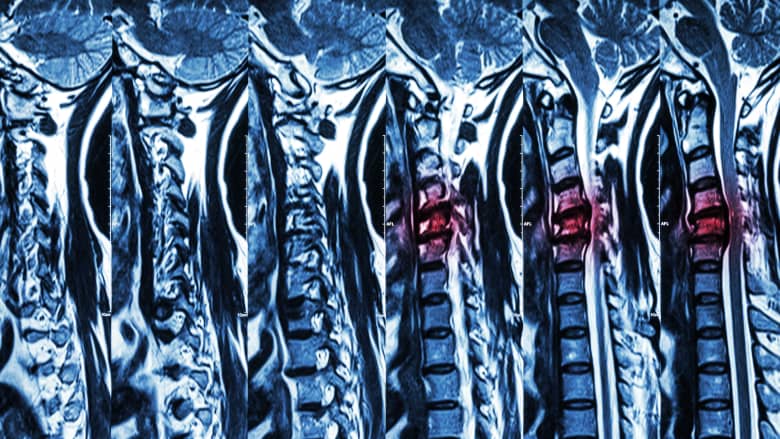

Magnetic resonance imaging (MRI) is used when high-resolution images of the body’s tissues are required for diagnosis and treatment.

For back or neck pain, MRI scans are a preferred diagnostic tool for investigating musculoskeletal problems with or without neurologic deficits when previous imaging is suggestive of spinal pathology. However, the presence of certain implants or prostheses may interfere with the MRI process, making it a health risk.